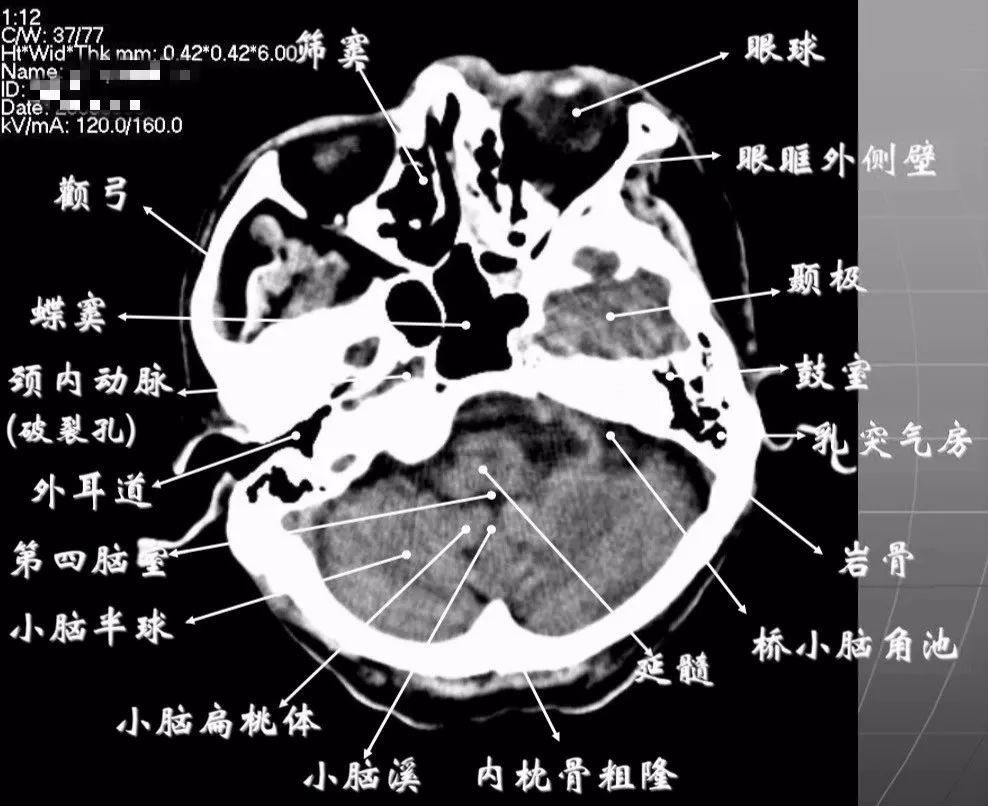

多图桥小脑角区正常影像解剖及常见病变

影像必备桥小脑角区正常解剖及常见病变